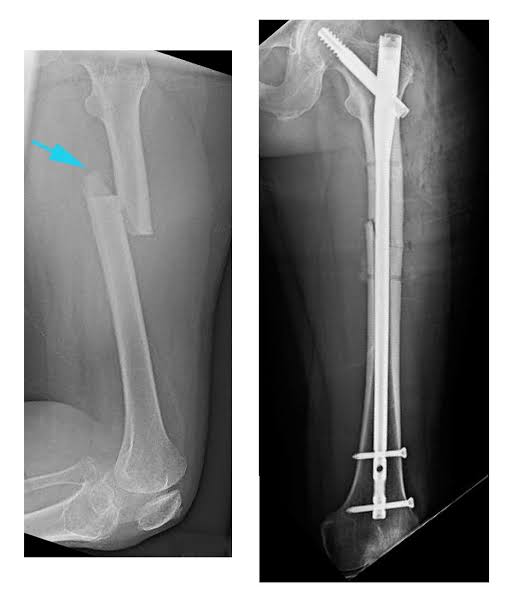

We do treatments for any kind of Accidental Fracture to give Patient's relief.